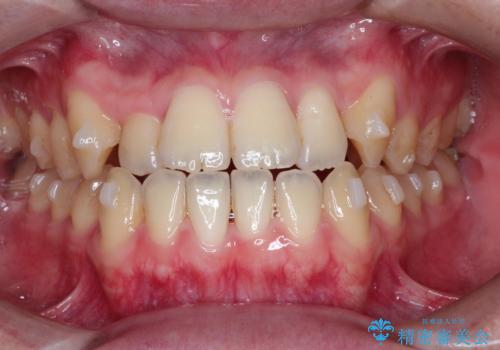

前歯のデコボコ インビザラインによる目立たない矯正

- 前歯のデコボコを主訴に来院された患者様です。

目立たないそうちをご希望されたので、インビザラインにて治療することとしました。

歯と歯の間をわずかに削ってスペースをつくり、デコボコを改善しました。